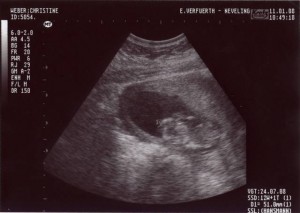

In der 12ten Woche war ich schon 51mm groß … und man konnte meinen Herzschlag als Blinken sehen.